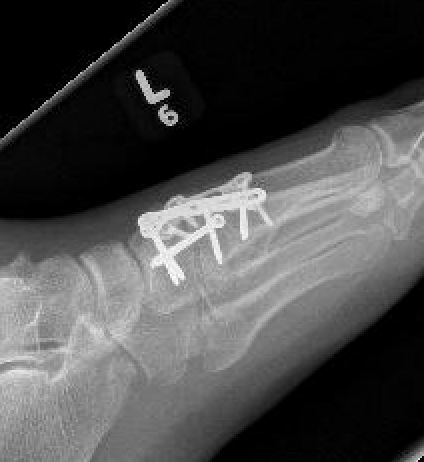

Bridge plate

Bridge plate to 1st TMT and second TMT with Lisfranc screw